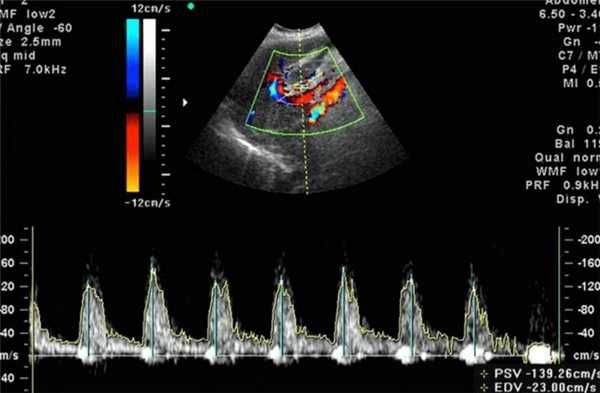

Допплерометрия плода выявляет патологии кровотока при беременности

Доплерометрия при беременности - это современный метод диагностики при помощи ультразвука, позволяющий объективно и полноценно исследовать кровообращение плода, плаценты и матки. По состоянию кровеносной системы можно оценить состояние плода, скорость его развития — не страдает ли малыш от недостатка кислорода, а также возможные патологические изменения. Допплерометрия плода — единственная методика, способная показать точное нахождение патологии сосудов (в матке, пуповине или плаценте).

Суть метода

Этот способ изучения кровеносной системы основан на применении эффекта Доплера.

Для обследования используется такой же ультразвук, как и при обыкновенном ультразвуковом исследовании. Отличие заключается в особом датчике, работающем на основе допплеровского эффекта, и интерпретации полученных данных. При исследовании фиксируются ультразвуковые волны, отраженные не от статичных тканей, а от подвижных объектов - клеток крови, в результате чего частота отраженных лучей сильно изменяется в сравнении с изучаемыми. Аппарат обрабатывает полученные данные и создает двухмерное цветное изображение. Благодаря этому возможно оценить скорость и направление кровотока, анатомию и проходимость сосудов.

Расшифровка результатов допплерометрии плода

Оценка состояния кровоснабжения с помощью допплера формируется на основе следующих показателей:

- Систоло-диастолическое отношение - отношение максимальной и минимальной скорости кровотока;

- Индекс резистентности - отношение разницы максимальной и минимальной скорости кровотока к максимальной в период сжатия;

- Пульсационный индекс - отношение разницы максимальной и минимальной скорости кровотока к средней скорости за полный цикл сердца.